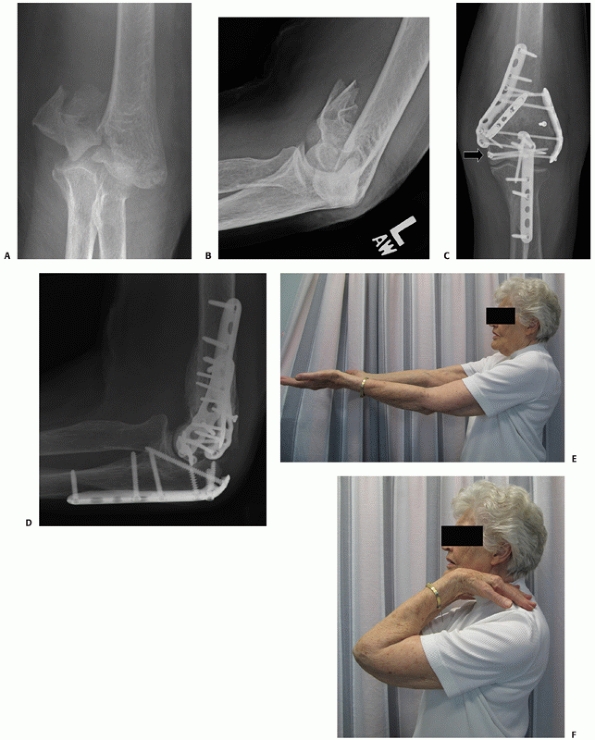

![]() |

FIGURE 33-19 Anteroposterior and lateral radiographs (A,B)

of a comminuted intra-articular distal humerus fracture (AO/OTA type C3) in an active 85-year-old woman. The articular fragments were first fixated with two (black arrow) centrally placed screws along the capitellar-trochlear axis (C,D). The reduced articular segment was then fixated to the shaft with triple plating. At 12 months follow-up, the fractures have healed and the patient has functional range of motion (E,F). |